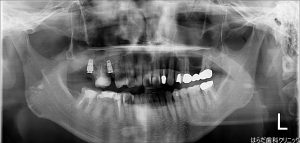

下記がオペ後のレントゲンのお写真です。

{12690-20160605[00](0)}C

しっかりと埋入されています。